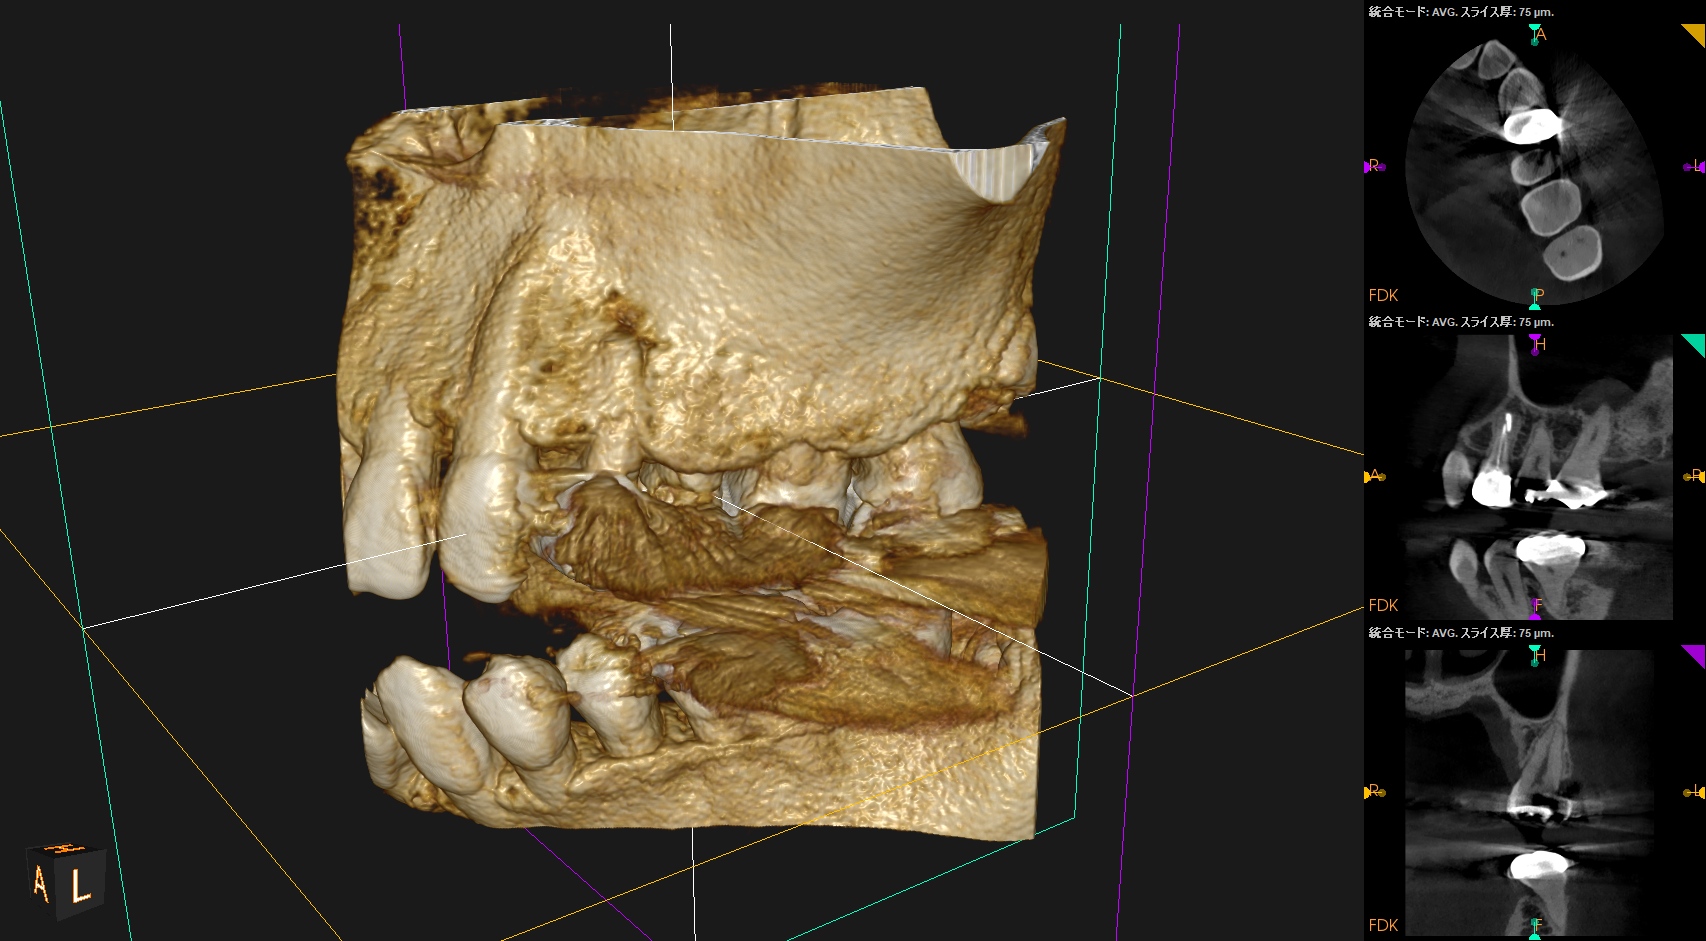

以下のようなケースでも可能なのだろうか?

例えPAやCBCTで根管が見えていても、だ。

CBCTを分析すれば、だ。

術後にPA, CBCTを撮影した。